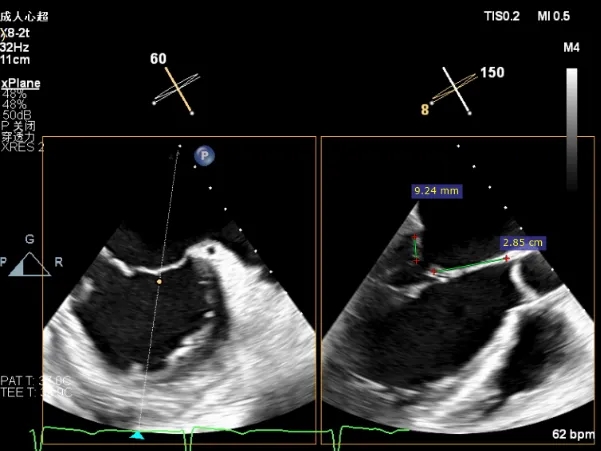

后叶长度9.24cm

可用房间隔穿刺高度4.03cm